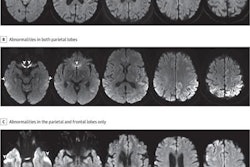

DTI-MR images are examples of the corpus callosum and its substructures -- genu (blue), body (green), and splenium (red) -- used in this study, as defined by software from Johns Hopkins University. Image courtesy of the European Journal of Radiology.Through DTI, the researchers targeted mean fractional anisotropy values in the corpus callosum and its substructures -- genu, body, and splenium -- which are believed to serve an important role in cognition and neural communication. Structural MR images were used to score the severity of brain injuries based on the number of lobes affected, volume and type of white-matter injury, and grey-matter damage.